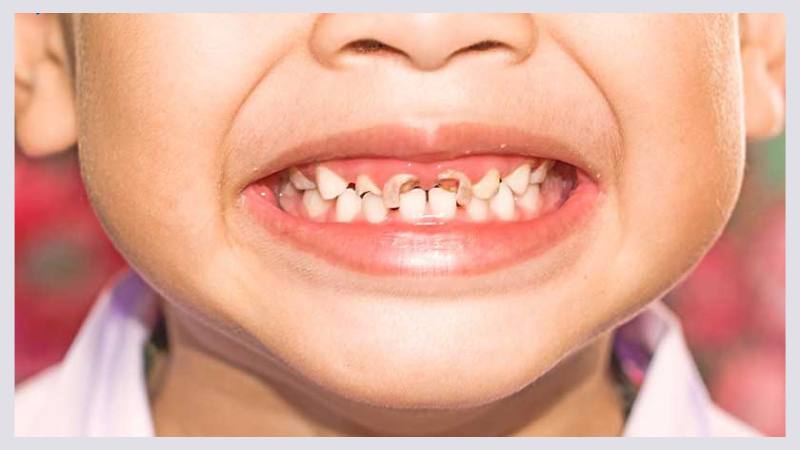

Sâu răng phát sinh do sự tấn công của vi khuẩn gây hại lên men răng. Từ đó ảnh hưởng đến ngà răng, lợi và các khu vực nằm liền kề. Hệ quả là có thể làm xuất hiện các cục màu trắng ở khu vực chân răng. Nếu không can thiệp nhanh để xử lý ổ viêm thì rất dễ dẫn đến viêm tủy răng ở mức độ nghiêm trọng.